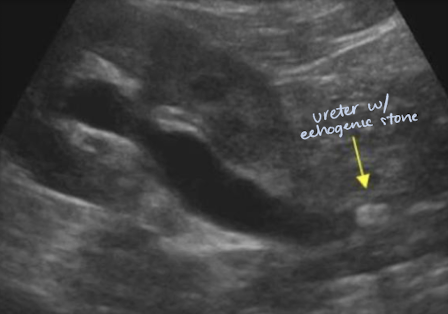

ureters

retroperitoneal structures that exit the kidneys to carry urine to the urinary bladder

begins as expanded upper area of renal pelvis

urine enters bladder via the ureters every several seconds or minutes

SONO: not seen unless obstruction present

SONO: “jets” in bladder